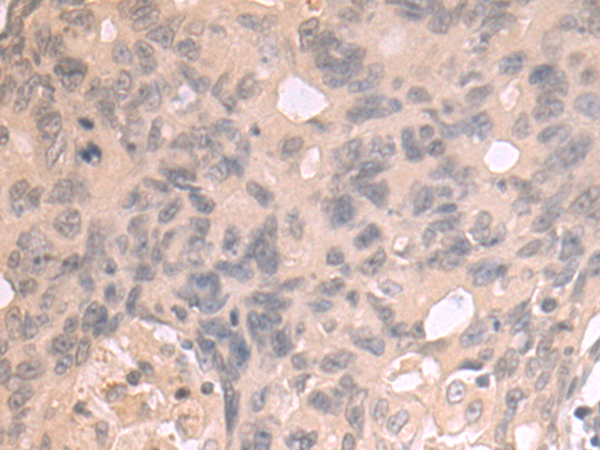

分类: 科研抗体货号: P07511别名: RK; p38; CSBP; EXIP; Mxi2; CSBP1; CSBP2; CSPB1; PRKM14; PRKM15; SAPK2A; p38ALPHA应用: IHC反应种属: Human, Mouse, Rat